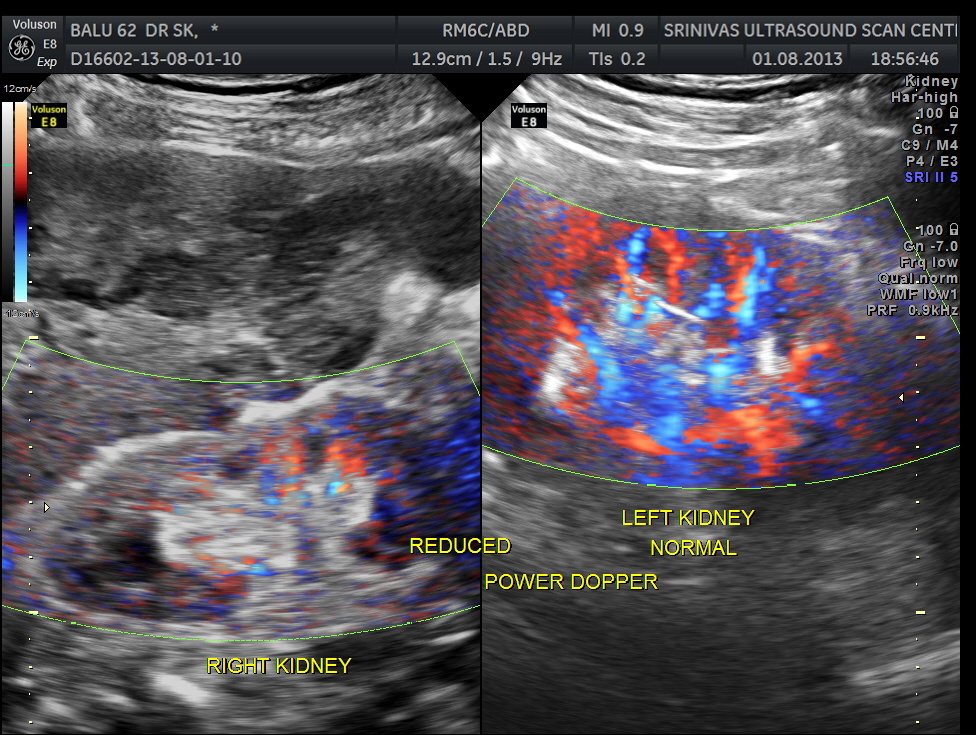

Clinically he had uncontrolled systemic hypertension and mildly elevated s. creatinine of 1.7 mgms/dl.

The diagnosis offered was multiple liver secondaries with incidental finding of shrunk right kidney with probable reduced function.